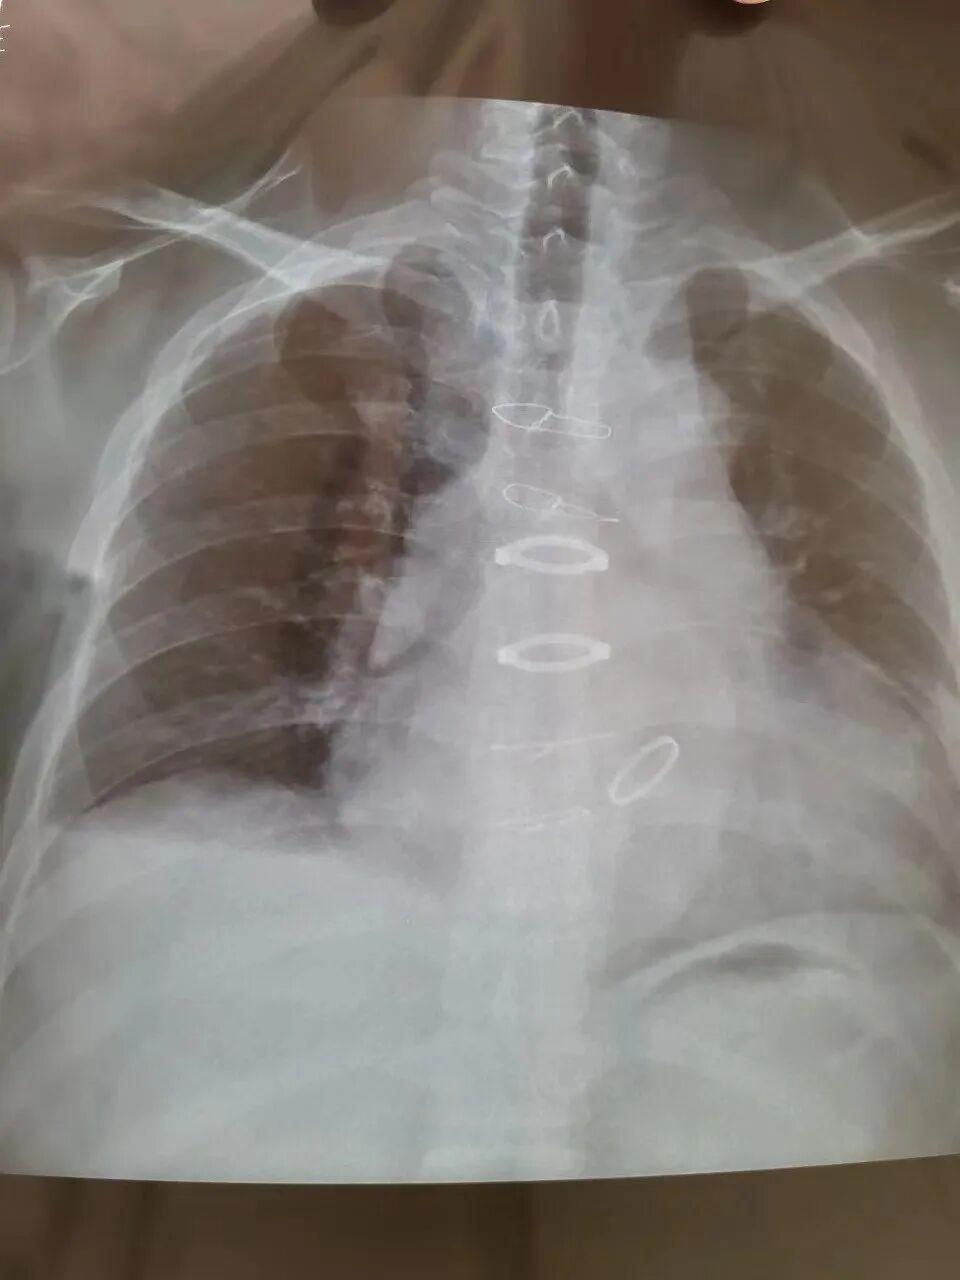

幾天前我們去醫院查血的時候又拍了個胸片,做了個心電圖,顯示心律正常,一切恢復良好。

胸片和心電圖顯示一切恢復良好丨作者供圖